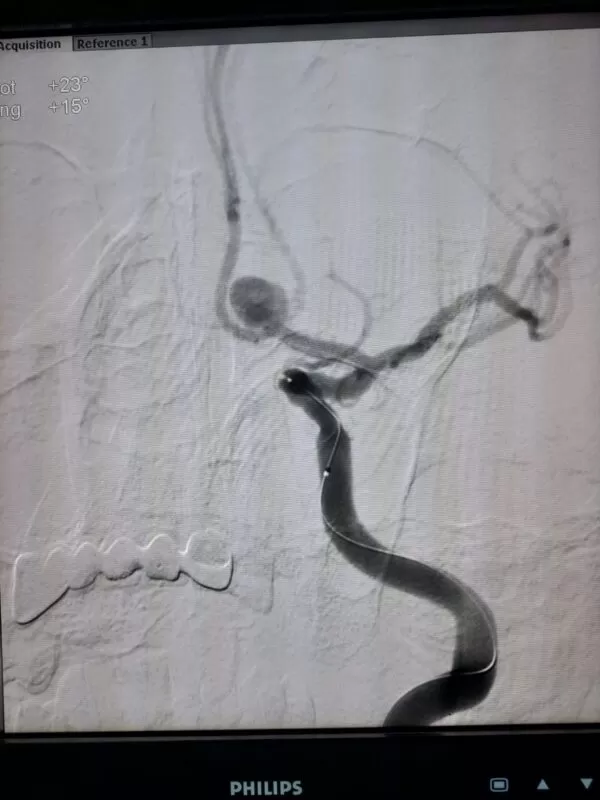

- القسطرة المخية التشخيصية

يتحدد القرار العلاجي في هل يعالج التمدد الشرياني المخي بالقسطرة المخية أم بالجراحة بناءً على حجم التمدد ومكانه والحالة الصحية للمريض.

القسطرة المخية التشخيصية (قسطرة المخ الاستكشافية)

دكتور أحمد الغيطي يعد القسطرة المخية هي المرجع الرئيسي للكشف عن أي اضطراب في الشرايين والأوردة المخية.

يجري دكتور أحمد الغيطي القسطرة المخية تحت تأثير التخدير الموضعي لدى معظم الحالات وفي المقابل قد يتم الإجراء تحت تأثير التخدير الكامل في حالة وجود اضطراب في وعي المريض.

يعتمد هذا الإجراء على إدخال أنبوبة رفيعة للغاية عبر ثقب صغير في منطقة أعلى الفخذ حيث تعبر خلال الشريان الأورطى ومنه إلى شرايين المخ ويقوم د\كتور أحمد الغيطي بإرشاد وتوجيه القسطرة التشخيصية أثناء هذه الخطوات بالأشعة السينية.

- علاج التمدد الشرياني بقيام دكتور أحمد الغيطي بوضع الملفات الحلزونية لغلق التمدد بصفة نهائية ومنع تدفق الدم خلاله لتجنب حدوث نزيف بالمخ.

- أحيانا يقوم دكتور أحمد الغيطي بعلاج التمدد الشرياني كبير الحجم باستخدام الدعامات المخية المضفرة التي تغير مسار الدم هذه الدعامات تكون عبارة عن أنابيب رفيعة لديها فتحات ضيقق للغاية لا تسمح بمرور الدم من خلالها وبالتالي لايصل إلى التمدد الشرياني أو استخدام القسطرة البالونية ذات المرونة العالية لغلق الشريان المغذي للتمدد.